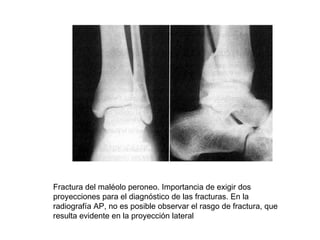

Fractura del maléolo peroneo. Importancia de exigir dos

proyecciones para el diagnóstico de las fracturas. En la

radiografía AP, no es posible observar el rasgo de fractura, que

resulta evidente en la proyección lateral

Fractura del maléoloperoneo. Importancia de exigir dos proyecciones para el diagnóstico de las fracturas. En la radiografía AP, no es posible observar el rasgo de fractura, que resulta evidente en la proyección lateral